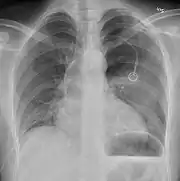

Chest X-ray

A plain chest radiograph, ideally with the X-ray beams being projected from the back (posteroanterior, or "PA"), and during maximal inspiration (holding one's breath), is the most appropriate first investigation.[30] It is not believed that routinely taking images during expiration would confer any benefit.[31] Still, they may be useful in the detection of a pneumothorax when clinical suspicion is high but yet an inspiratory radiograph appears normal.[32] Also, if the PA X-ray does not show a pneumothorax but there is a strong suspicion of one, lateral X-rays (with beams projecting from the side) may be performed, but this is not routine practice.[15][19]

It is not unusual for the mediastinum (the structure between the lungs that contains the heart, great blood vessels, and large airways) to be shifted away from the affected lung due to the pressure differences. This is not equivalent to a tension pneumothorax, which is determined mainly by the constellation of symptoms, hypoxia, and shock.[13]

The size of the pneumothorax (i.e. the volume of air in the pleural space) can be determined with a reasonable degree of accuracy by measuring the distance between the chest wall and the lung. This is relevant to treatment, as smaller pneumothoraces may be managed differently. An air rim of 2 cm means that the pneumothorax occupies about 50% of the hemithorax.[15] British professional guidelines have traditionally stated that the measurement should be performed at the level of the hilum (where blood vessels and airways enter the lung) with 2 cm as the cutoff,[15] while American guidelines state that the measurement should be done at the apex (top) of the lung with 3 cm differentiating between a "small" and a "large" pneumothorax.[33] The latter method may overestimate the size of a pneumothorax if it is located mainly at the apex, which is a common occurrence.[15] The various methods correlate poorly but are the best easily available ways of estimating pneumothorax size.[15][19] CT scanning (see below) can provide a more accurate determination of the size of the pneumothorax, but its routine use in this setting is not recommended.[33]

Not all pneumothoraces are uniform; some only form a pocket of air in a particular place in the chest.[15] Small amounts of fluid may be noted on the chest X-ray (hydropneumothorax); this may be blood (hemopneumothorax).[13] In some cases, the only significant abnormality may be the "deep sulcus sign", in which the normally small space between the chest wall and the diaphragm appears enlarged due to the abnormal presence of fluid.[16]